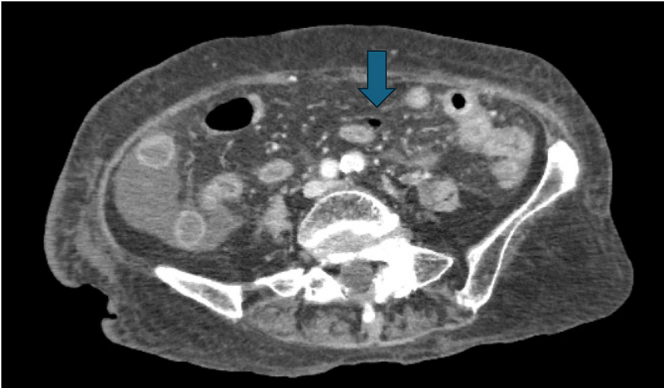

Clinical presentation: An 83-year-old woman with prolonged methotrexate and steroid use for rheumatoid arthritis was referred to our hospital due to hypotension, hypoxemia, and altered mental status following bloody stools. Endoscopy revealed a rectal hemorrhage. After hemostasis, the patient developed septic shock and diarrhea, raising suspicion of CMV colitis, which was confirmed by CMV antigenemia. Despite treatment with ganciclovir, the patient developed a diverticular perforation. Histological examination of the surgical specimen revealed localized infiltration of CMV-infected cells in the granulation tissue at the perforation site, without other inflammatory changes. The patient died from liver failure on the 28th day of hospitalization.

Clinical discussion: CMV colitis is reported in patients with autoimmune diseases and, in severe cases, can lead to gastrointestinal perforation. In this case, CMV infection caused diverticular perforation; however, autopsy revealed no significant inflammatory changes throughout the gastrointestinal tract. This suggests a highly localized CMV invasion, a rare clinical presentation.